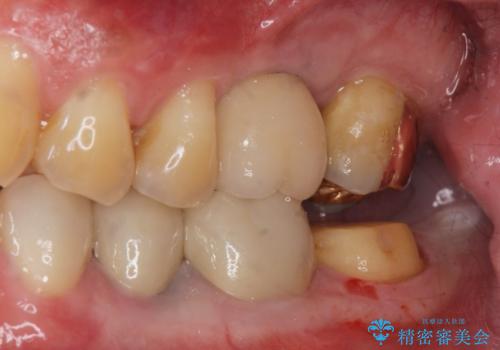

- 過去に治療したゴールドの詰め物が取れて来院。取れたのは2回目だそうです。レントゲンでは適合が良いので再装着可能だったが、

もう取れたくないとの事だったので被せ物のご案内をしました。ゴールドの被せ物の希望だったのでゴールドクラウンでの治療になりました。

適合の良いゴールドクラウンが入りました。

ゴールドは適合が良く、割れる心配もありません。

また、虫歯になるリスクも銀歯と比べて低くなります。